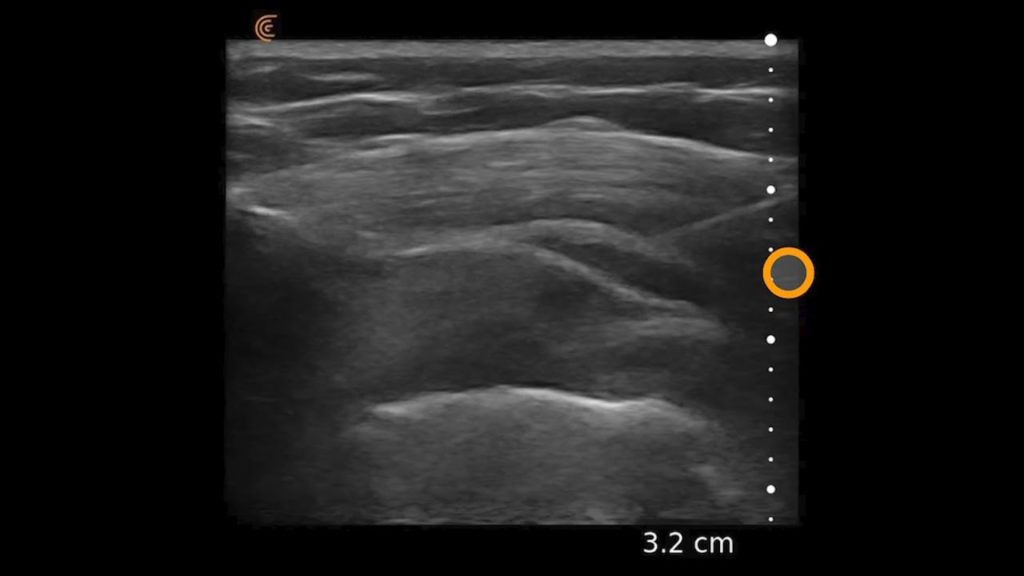

Using the jejunum as an important landmark, the hypoechoic jejunal lymph nodes can be identified. In this video Dr. Edwards explains the ultrasound appearance of normal jejunal nodes.